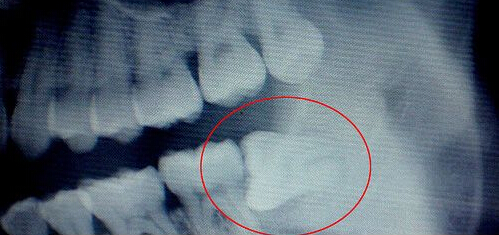

智齿对比照片:

智齿学名第三大臼齿,俗称智慧齿、立事牙、尽头牙,是口腔最靠近喉咙的牙齿,如果全部生长出来一共4颗,上下颚各两颗,一般是于16岁或之后才生长出来,相较于幼儿时期长出的乳齿与儿童时期更换的恒齿,智齿通常是在人类心智已经趋于成熟时才长出,因而得名。 症状在智齿的生长方面,个体差异很大,有的人20岁之前长出来,有的人40、50岁才长,有的人终生不长,这都是正常的。而且四颗智齿也不是都会长全,某些人的智齿可能只长1至2颗,有的智齿甚至长到一半就不再生长,这种情况称为智齿阻生。智齿的位置从门牙牙缝开始,由一侧门牙向里数牙齿数目,如果有第八颗牙,它就是智齿。>>>点击免费咨询,或者拨打24小时齿科健康热线0591-88681777咨询,贝臣齿科医师为您解答!

3.阻生智齿不但对全身有损害,对邻牙也有损害,常造成邻牙龋齿,严重时可产生牙髓炎,使邻牙牙槽骨受损而过早丧失功能。

微创无痛拔牙:微创拔牙是一种新的拔牙方式,通过全景数字扫描机对患牙进行全面拍摄,确定患牙位置,然后实施局部麻醉后,在无菌条件下操作,微创拔牙技术操作时间短,减轻了患者拔牙过程中的不适感觉,缩短了手术时间,消除患者紧张恐惧的心理,具有创口小、出血少、痛苦轻、术后并发症少的优点。微创拔牙新技术对复杂阻生智齿的拔除具有明显优势,避免了传统的劈冠凿骨和敲锤增隙,大大减轻了患者的不舒适感觉,使牙齿充分松动并轻松脱出。>>>还有不明白的,点击免费咨询,或者拨打24小时贝臣美牙热线0591-88681777咨询,贝臣齿科医师为您解答!